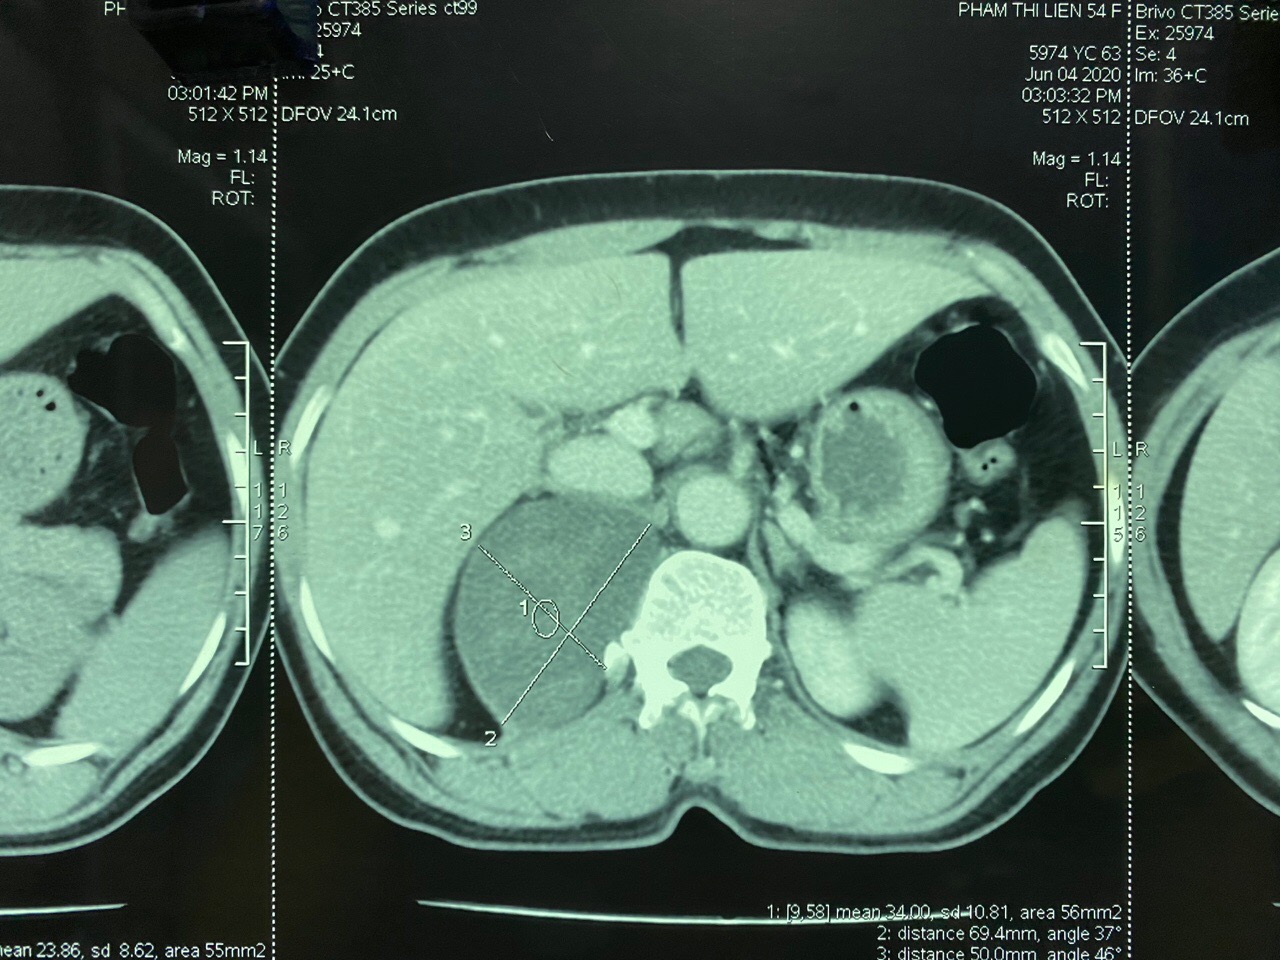

Ngay khi tiếp nhận bệnh nhân, các Bác sĩ của Bệnh viện Đa khoa tỉnh đã tiến hành thăm khám lâm sàng và cho bệnh nhân làm các xét nghiệm cơ bản và chuyên sâu. Kết quả xét nghiệm hormone ACTH, Cortisol, Catecholamin có kết quả bình thường. Hình ảnh chụp CT cho thấy phía sau phúc mạc phía bên phải cột sống, ngay cạnh và dưới tĩnh mạch chủ bụng, động mạch chủ bụng có vài khối giảm tỷ trọng kích thước 30x50x100 mm đè đẩy tuyến thượng thận phải, thận phải và tĩnh mạch chủ bụng, khối u này nằm sâu phía sau gan và trên thận. Bệnh nhân được chỉ định làm sinh thiết khối u bằng kim tru-cut dưới hướng dẫn của siêu âm, kết quả sinh thiết cho thấy đây là khối u sau phúc mạc thể Schwannoma.

Hình ảnh khối u trên phim chụp CT scanner